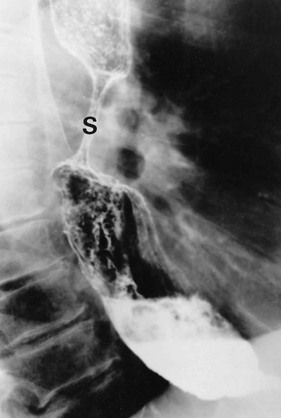

Pharyngeal pouch is a rare cause of dysphagia. It arises at the junction of pharynx and oesophagus, and probably results from lack of coordination between the inferior constrictor muscle and cricopharyngeus during swallowing. At this point, there is an area of relative weakness known as Killian's dehiscence. The result is a progressive mucosal outpouching between the two muscles. The condition is best diagnosed by barium swallow (see Fig. 22.10). Pharyngeal pouch is easily perforated during endoscopy, and therefore in endoscopy to investigate ‘high’ dysphagia, the procedure should be performed by an experienced endoscopist. Treatment of pharyngeal pouch is by surgical excision from the side of the neck, or via a completely endoluminal approach using a stapler to join the pouch to the oesophagus.